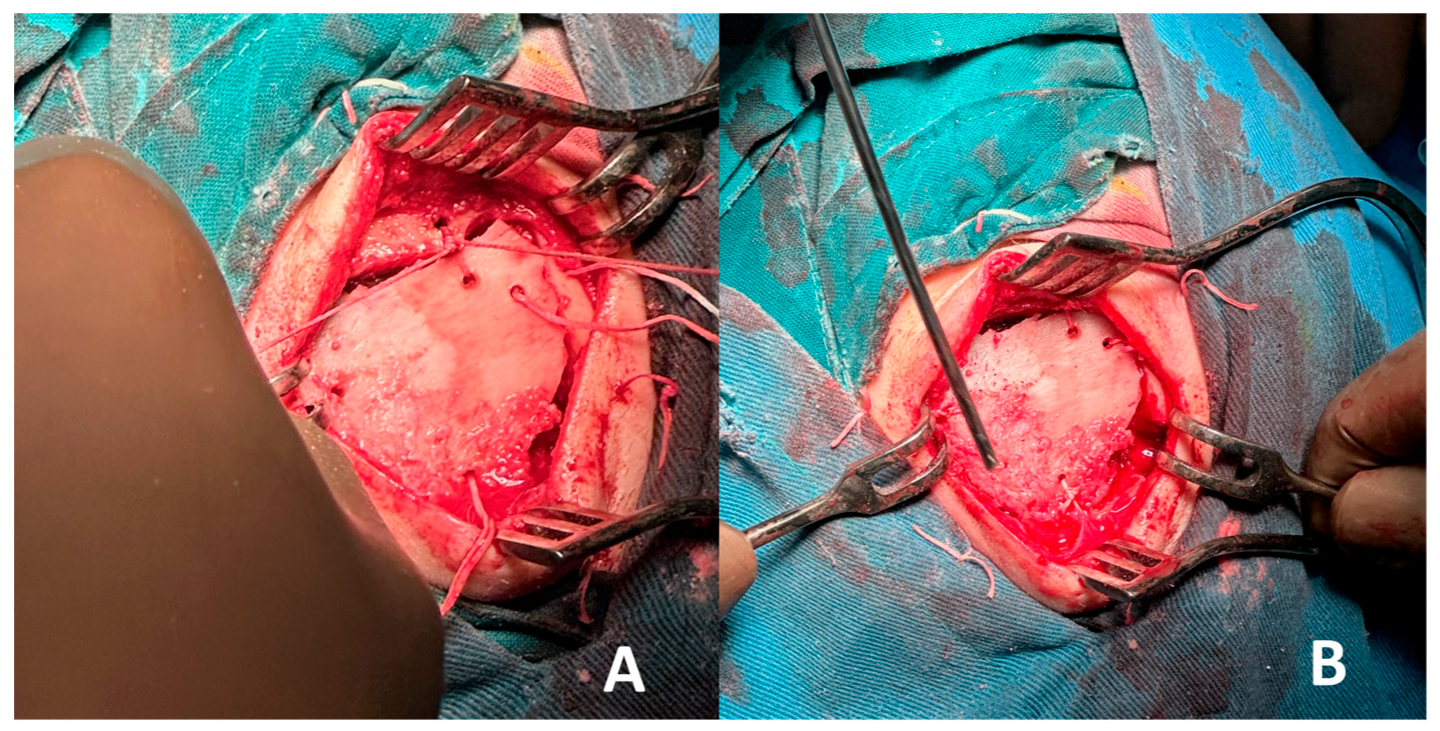

2. Case Report